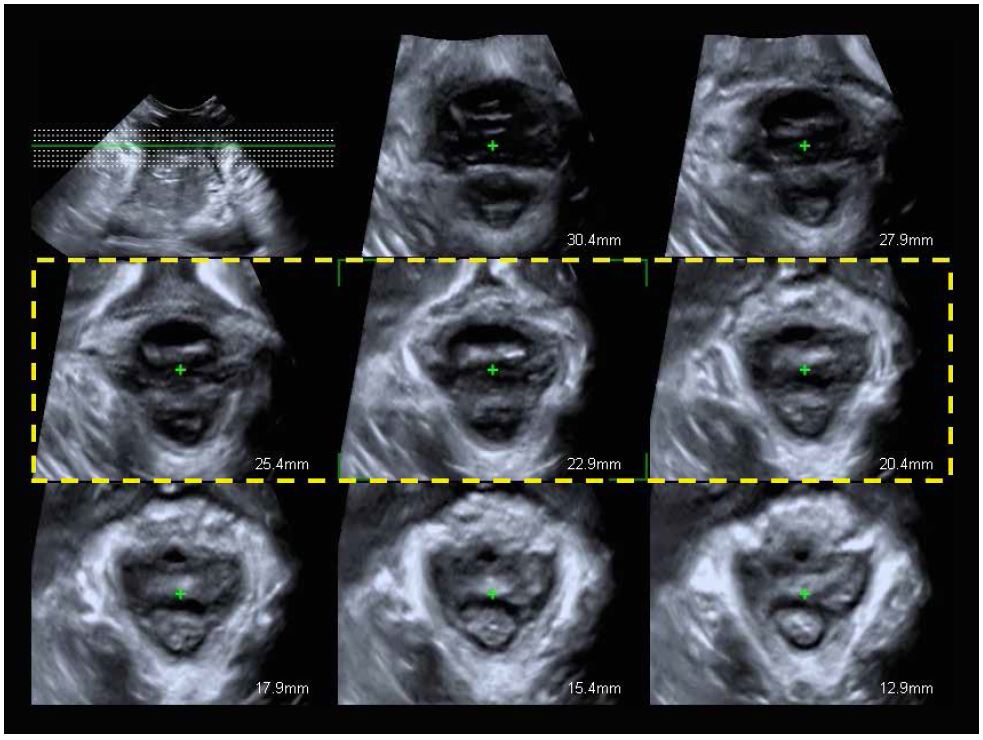

Мультиплощинна реконструкція з площини мінімальних гіатальних розмірів (мал. 10) є стандартизованим і еталонним способом оцінки авульсії LAM. Осьові площини отримують з інтервалом 2,5 мм (5 мм каудально і 12,5 мм краніально), оцінюючи загалом 8 площин (мал. 11). Точне розташування 8 площин встановлюється по трьох центральних площинах (жовта пунктирна лінія на мал. 11):

• 1st прощина (зліва): дуги лобкового симфізу розділені.

• 2nd площина (центральна): дуги лобкового симфізу зімкнуті.

• 3rd площина (справа): лобок не повинен відображатися, заміняючись акустичною тінню.

Малюнок 10. Площина мінімальних розмірів діафрагми. P: Лобок, U: Уретра, V: Піхва, AC: Анальний отвір, LAM: М'яз-підіймач відхідника

Малюнок 11. Багатоплощинна реконструкція м'язу-підіймача відхідника (LAM) з трьома центральними площинами, виділеними жовтим.

Авульсія LAM визначається як відшарування м'яза від лобкової області. Воно є повним, коли воно присутнє в трьох центральних площинах, і частковим, коли є пошкодження м’язів в інших площинах без відповідності критеріям повного відриву.